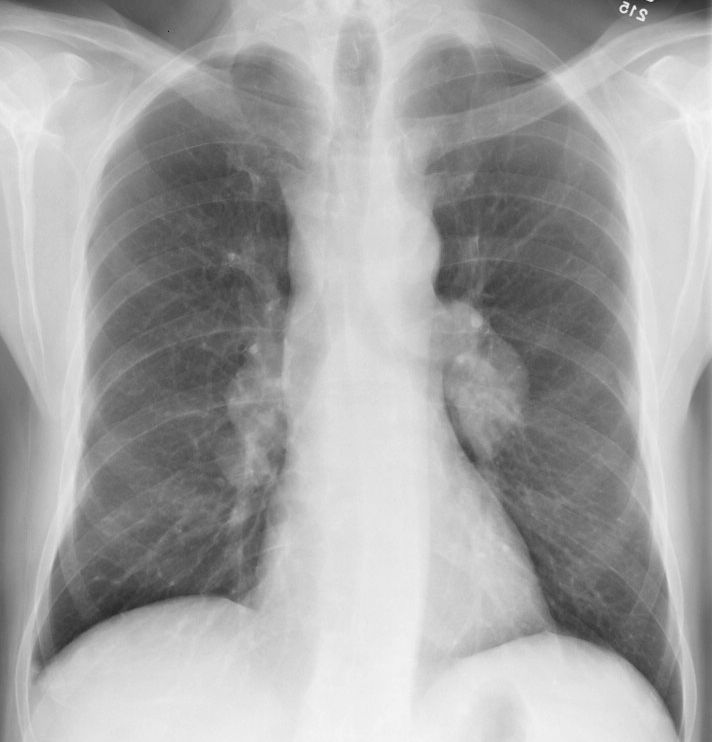

Gallery Mediastinum Lymphoma 9a

9a